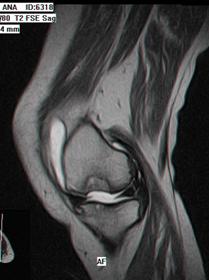

1.2.3. Rezonanta Magnetica Nucleara

Rezonanta Magnetica Nucleara (RMN) este in prezent investigatia imagistica de electie in diagnosticul si evaluarea leziunilor condrale.

Secventele standard T1 fast-spin nu sint sensibile in evaluarea leziunilor cartilajului articular, insa secventele T2 fast-spin si T1 densitate protonica cu supresie a grasimii sint atit specifice cit si senzitive in decelarea leziunilor cartilajului articular (fig. 1.5) Cea mai mare specificitate este la nivelul cartilajului articulatiei femuropatelare datorita grosimii cartilajului (fig. 1.6)

In Figura 1.9 si Figura 1.10 se pot observa leziuni de osteocondrita disecanta a condilului femural intern si extern, evidentiabile pe diferite sectiuni si secvente RMN.

Fig1.9 Imagine RMN sectiuni sagitale si transversala la nivelul genunchiului, leziune de osteocondrita disecanta a condilului femural intern |